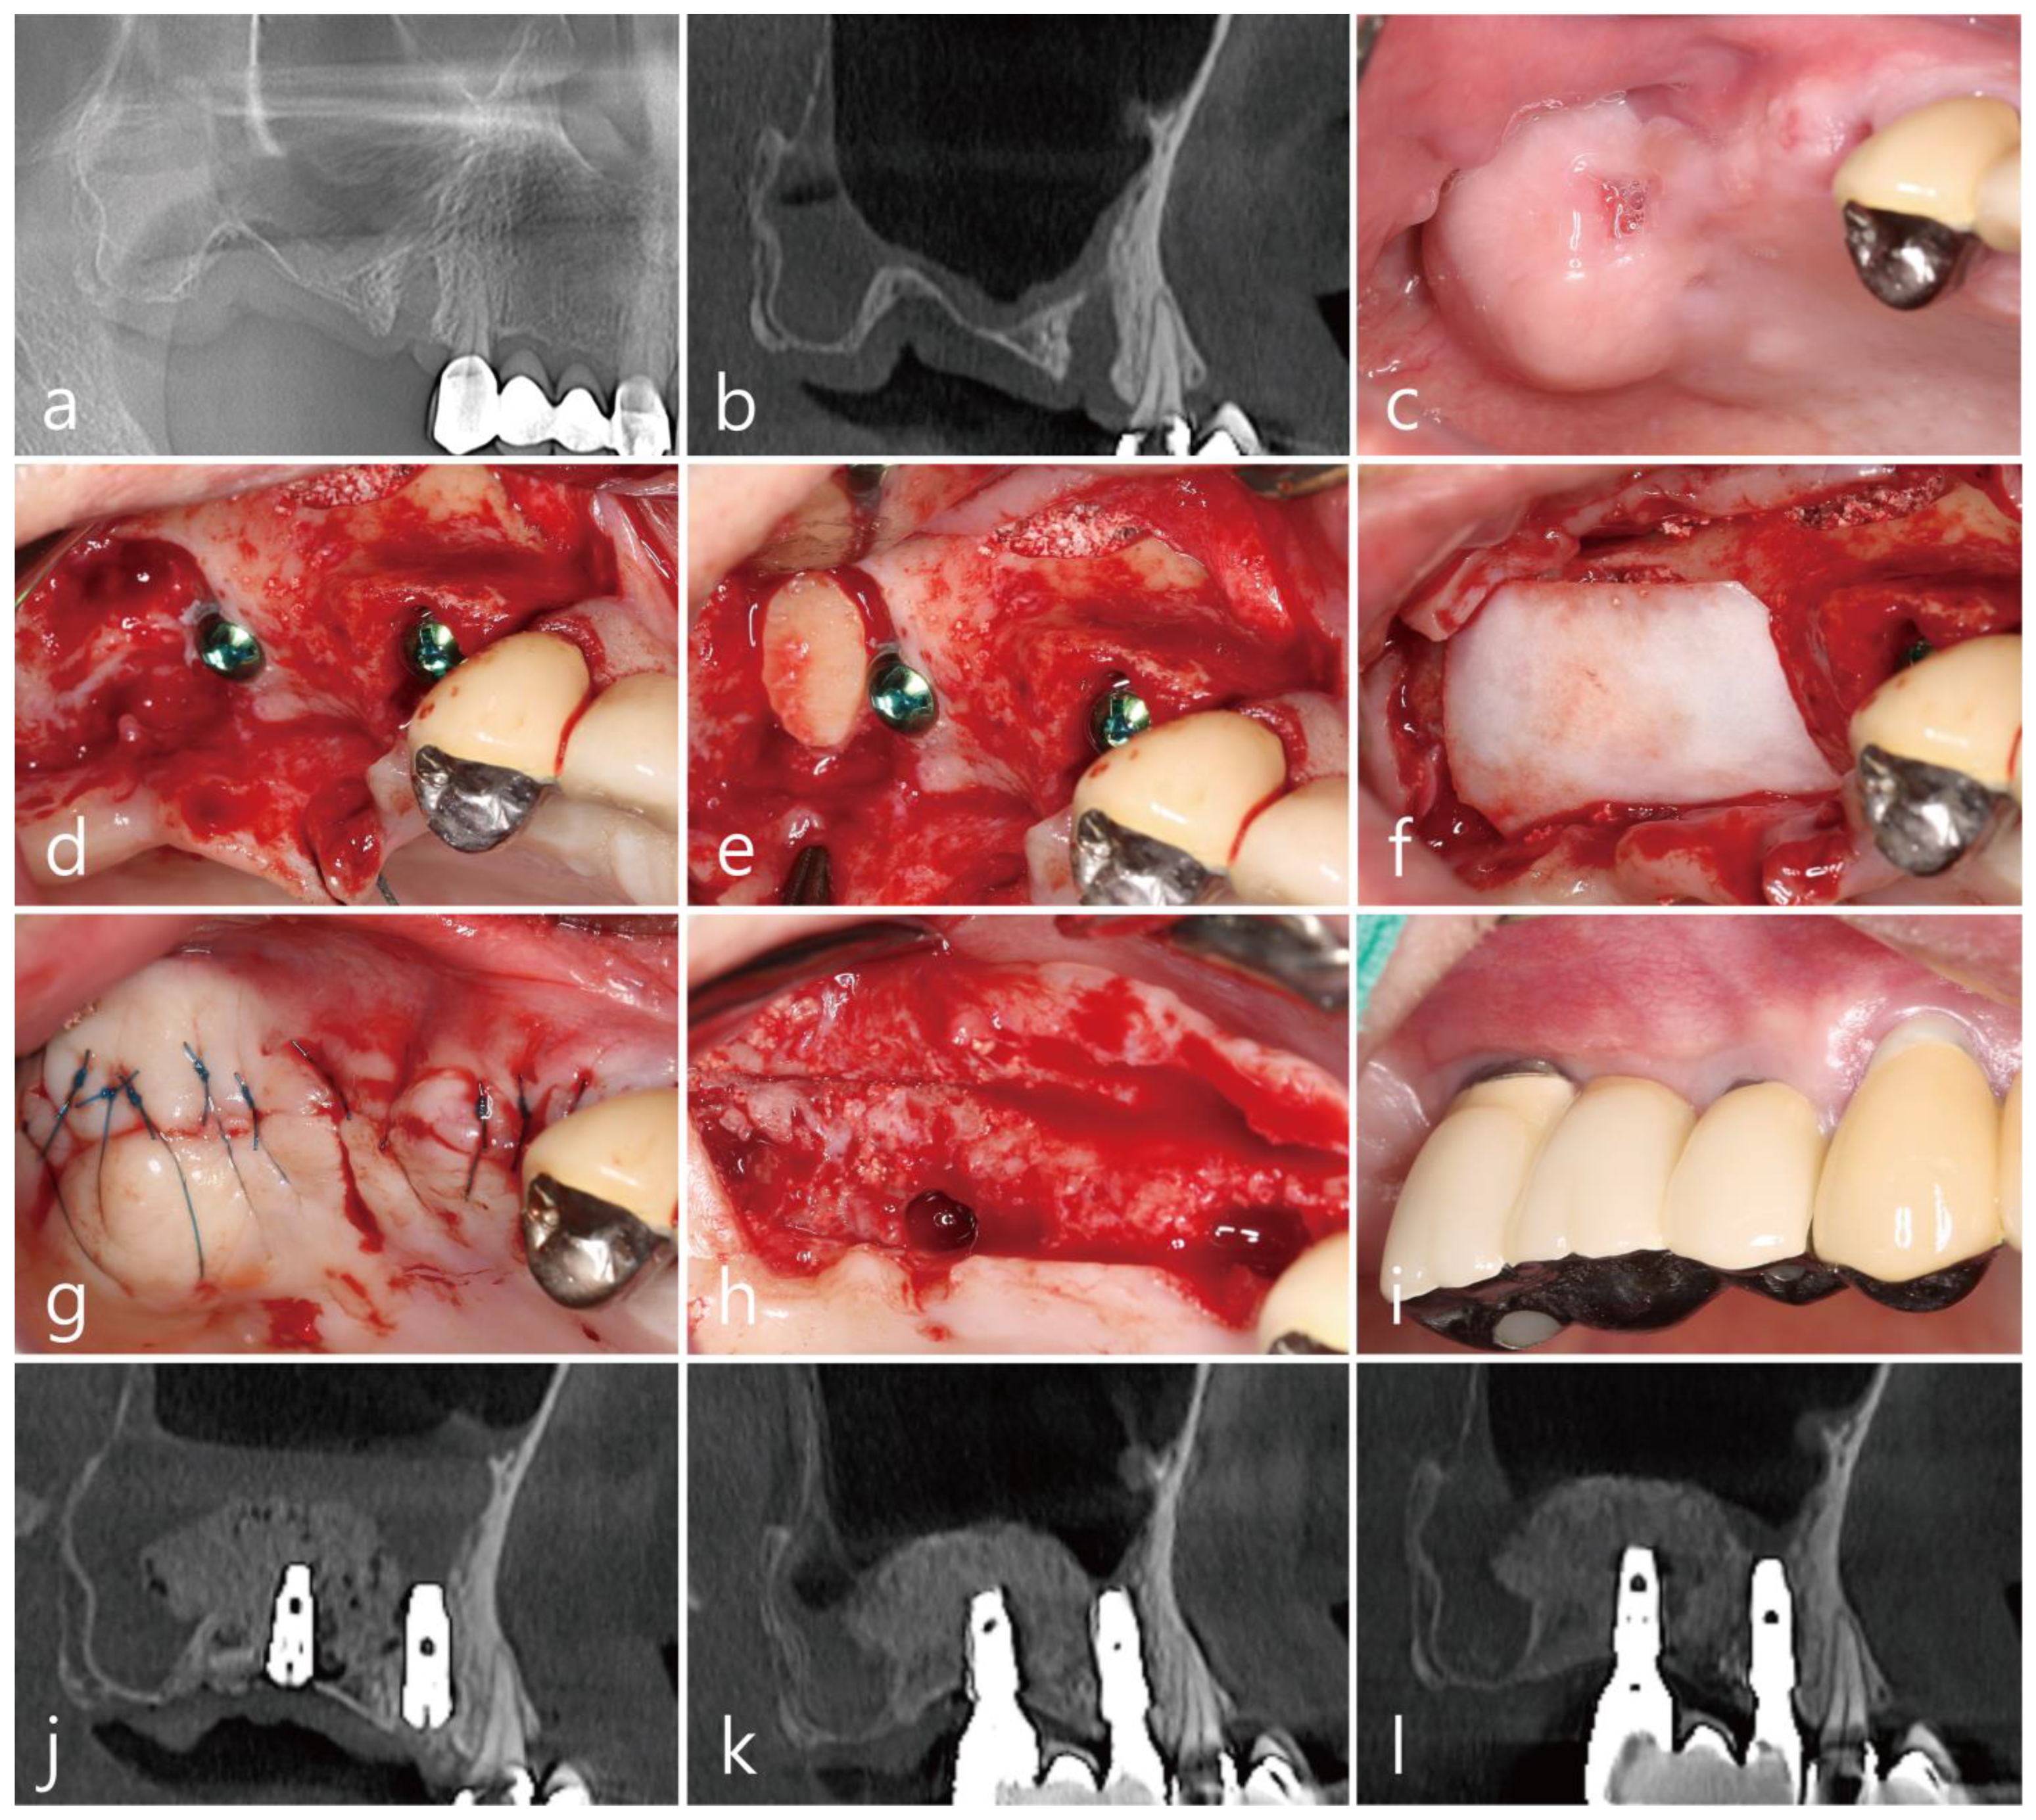

The patient was a 78 year old nonsmoking woman, who visited the clinic for implant placement in the left maxillary posterior region (Table 1). The patient was taking antihypertensive drugs and had no other diseases that could interfere with the surgery. Two months after the extractions of #25 and #26, panoramic radiographs and CBCT scans showed severe bone deficiencies in the extraction sockets (Figure 2a,b). There was no PSAA in the lateral sinus wall (Table 1). The preoperative clinical photographs revealed severe deficiencies of the hard and soft tissues of the extraction sites (Figure 2c). Under local anesthesia with 2% lidocaine (containing 1:100,000 epinephrine), the mucoperiosteal flaps were reflected, and the lateral bony window obtained during MSA was removed (Figure 2d). There was no perforation of the maxillary sinus mucosa during MSA. The extraction socket had a severe bone defect. Thorough debridement was performed to remove inflammatory granulation tissue (Figure 2e). After the MSA procedure was performed, the post-extraction defect was augmented using a particulate bone graft substitute (Osteon™ III; particle size 0.2–0.5 mm; Genoss Co., Ltd., Suwon, Republic of Korea) was performed. Then, a lateral window bone was appropriately trimmed using a grinder (Dask kit, Dentium Co., Ltd., Suwon, Republic of Korea) and was placed in the extraction defects of #25 and #26 (Figure 2f). The bone graft site was covered with a resorbable collagen membrane (Genoss Co., Ltd., Suwon, Republic of Korea) (Figure 2g), and the flaps were closed with 5-0 sutures (Figure 2h). Antibiotics (ciprofloxacin; 500 mg; Ildong Pharmaceutical Co., Ltd., Seoul, Republic of Korea) and a nonsteroidal anti-inflammatory drug (Etodol; 200 mg, Yuhan Co., Ltd., Seoul, Republic of Korea) were prescribed for two weeks. A total of 0.12% of chlorhexidine (hexamedine; Bukwang Pharmaceutical, Seoul, Republic of Korea) mouth rinsing was recommended twice a day for two weeks. Two weeks after surgery, a sinus graft infection occurred, and incision and drainage were performed at the lateral window site. An additional antibiotic (ciprofloxacin; 500 mg; Ildong Pharmaceutical Co., Ltd., Seoul, Republic of Korea) were administered for 7 days. Saline irrigation was performed once a week for six weeks. The implant was placed six months after the MSA. Due to the sinus graft infection, some resorption occurred in the grafted area of the lateral sinus window, and an additional bone graft was performed (Figure 2i). The uncovering procedure was performed six months after the implant placement. The preoperative bony defects were filled to the top of the cover screw (Figure 2j). A prosthesis was delivered two months after the uncovering procedure (Figure 2k).

The preoperative sagittal CBCT scan revealed severely resorbed extraction sockets of #25 and #26 (Figure 2l). On the sagittal image of the CBCT immediately after surgery, the lateral window bone obtained during MSA was located at the entrance of the extraction socket (Figure 2m). The sagittal CBCT scan one year after the prosthesis delivery revealed homogeneous bone filling compared to the previous CBCT scans (Figure 2n).

Figure 2. Case 2: (a) preoperative panoramic radiograph; (b) preoperative panoramic image of the CBCT scan showing a severely resorbed bone defect and a pneumatized maxillary sinus on the left side; (c) preoperative clinical view at two months after extraction of the left maxillary second premolar and first molar; (d) after reflection of the mucoperiosteal flap, the lateral bony window was obtained; (e) thorough debridement was performed to remove inflammatory granulation tissue; (f) after maxillary sinus augmentation, an appropriately trimmed lateral bony window was placed on the defect, and the gap was filled with particulate bone graft; (g) the grafted site was covered with a collagen membrane; (h) the mucoperiosteal flaps were closed with minimal tension; (i) implants were placed six months after the surgery, and additional bone grafting was performed at the lateral window site where bone loss had occurred due to the sinus graft infection; (j) the uncovering procedure was performed six months after implant placement; (k) a prosthesis was delivered two months after the uncovering procedure; (l) preoperative sagittal image of the CBCT scan; (m) sagittal images of the CBCT taken immediately after surgery; (n) sagittal image of the CBCT one year after prosthesis delivery.